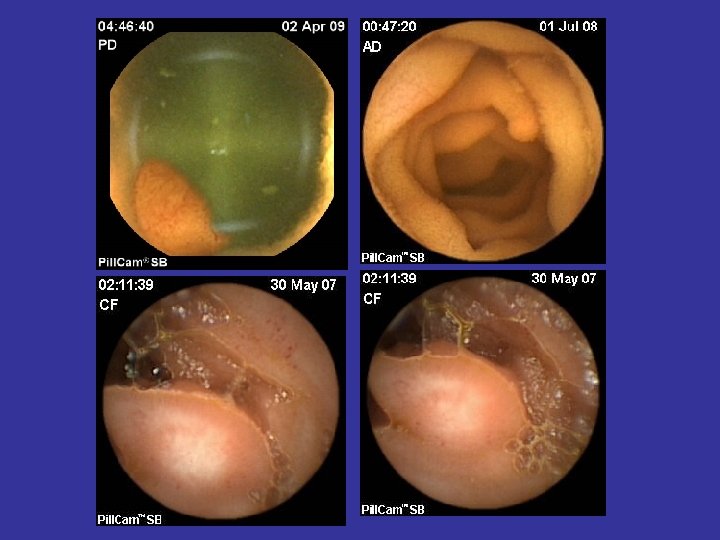

Tipuri de leziuni depistate in BC • • Eroziuni Edem mucosal Congestie parcelara Ulceratii aftoide; Ulcere liniare/ neregulate/ confluente; Pseudopolipi inflamatori; Stenoze inflamatorii;